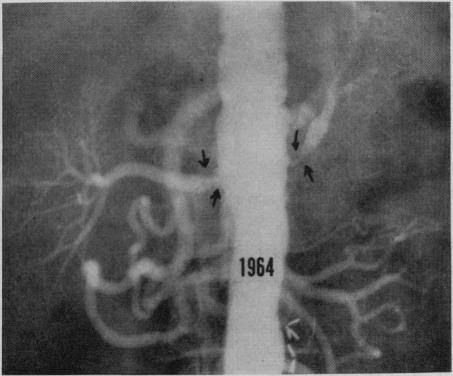

Recurrent renovascular hypertension: report of two cases with long-term follow-up.

Can Med Assoc J. 1969 Feb 22;100(8):363-70.